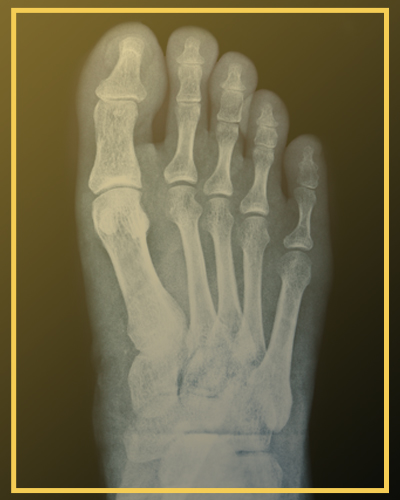

Alguém que sempre teve dor na região plantar dos pés, embaixo da cabeça dos dedos. Com o passar do tempo foi formando uma calosidade cada vez maior, com a dor piorando tanto ao ponto de ele não conseguir andar muito tempo na praia ou descalço. Ao fazermos uma radiografia veio o diagnóstico: índex minus – alguém sabe o que é isso?

A fórmula metatarsal diz respeito ao tamanho dos metatarsos, os ossos que formam os raios dos nossos pés e de onde se originam os dedos.

• Índex minus (primeiro metatarso mais curto): também chamado de “pé de Morton”. Se o primeiro metatarso é menor do que o segundo pode ocorrer o apoio na cabeça do 2o raio, por ser mais longo, podendo ser a causa da metatarsalgia primária

Apesar de existirem métodos de análises baseados em medidas e arcos, uma radiografia dos pés (que deve ser feita com apoio) já nos dá uma ótima ideia de fórmula metatarsal de cada paciente .